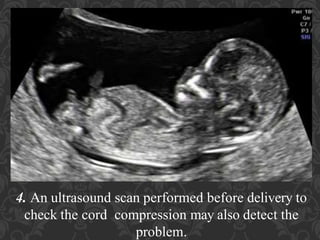

38. 4. An ultrasound scan performed before delivery to check the cord compression may also detect the problem.

39. 5. Prenatal ultrasound scans are able to detect any abnormality in the developing fetus. If umbilical cord prolapse is detected, it will show an abnormal position of the cord in the birth canal.